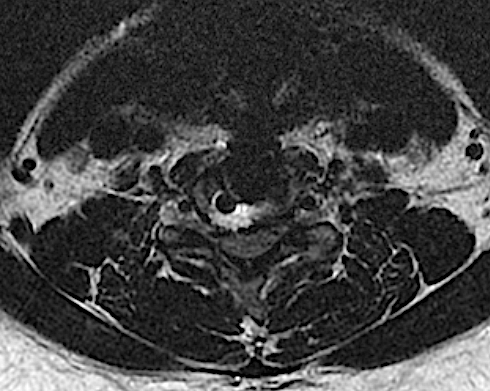

Sección axial C6-C7. Obsérvese el área hiperintensa en T2 que se corresponde con la resección de platillo posterior C7. La caja se lateralizó ligeramente a la izquierda.

Obsérvese la ocupación de canal >50%, sobre todo en la mitad derecha